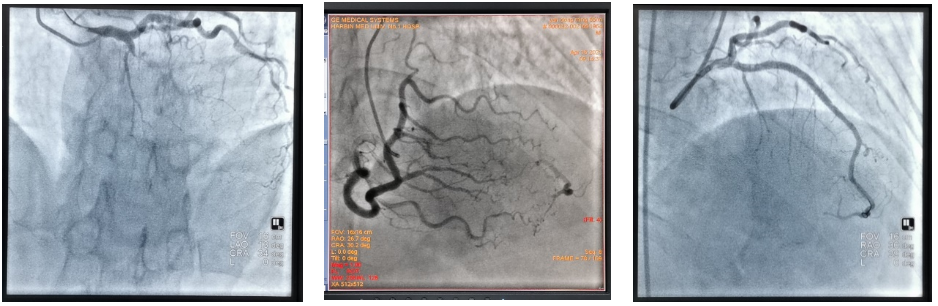

病例三:65岁男患前降支血管慢性完全闭塞(左图)。顺利开通完全闭塞血管,于前降支置入支架2枚,造影示术后血流完全恢复(右图)。